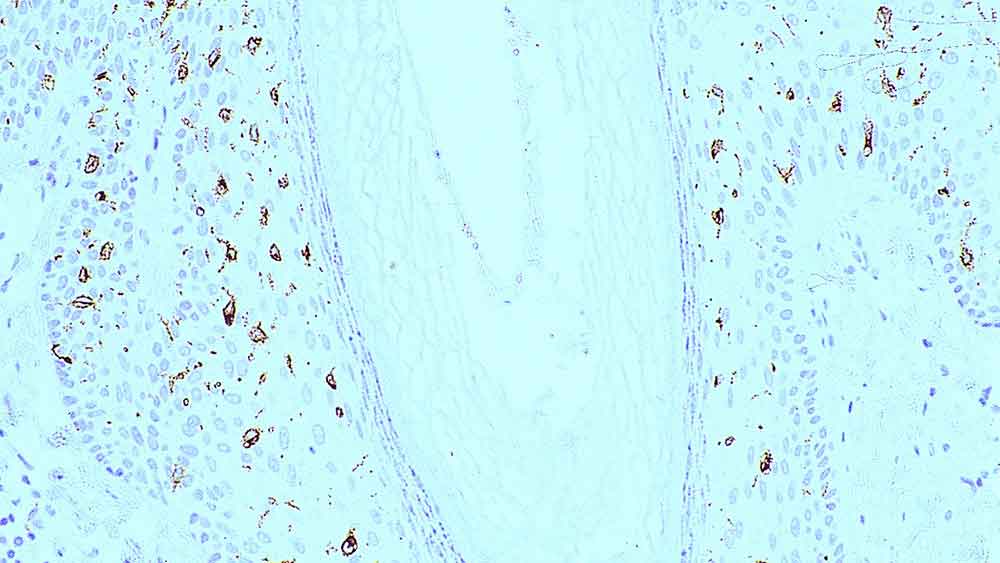

クロモジェン

染色タイプ/アプリケーション